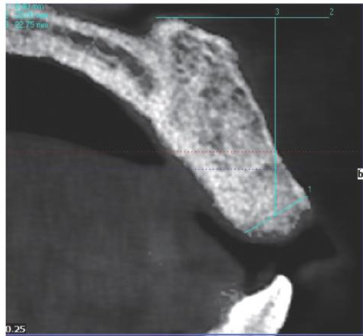

[摘要]牙吸收是在破牙细胞持续作用下发生的牙齿硬组织破坏。牙颈部外吸收是由于牙周膜或上皮下牙骨质破坏和(或)缺陷导致的牙齿颈部吸收。本文报道1例上颌中切牙外伤及正畸后牙颈部外吸收,术前通过锥形束CT充分了解患牙吸收部位和形态,术中利用显微技术及生物陶瓷和复合树脂材料分层修补对吸收部位进行严密充填修复,实现了保存患牙和尽可能长时间保存患牙健康牙髓的目标,术后6年随访效果良好。